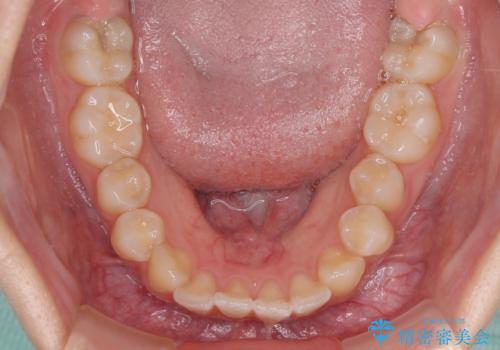

- 前歯のデコボコと磨きにくい奥歯を気にして来院された患者様です。

左右ともに上顎第二大臼歯が外側に転位しており、大変磨きにくくなっているため、補助装置により内側に引き込むことで改善することとしました。